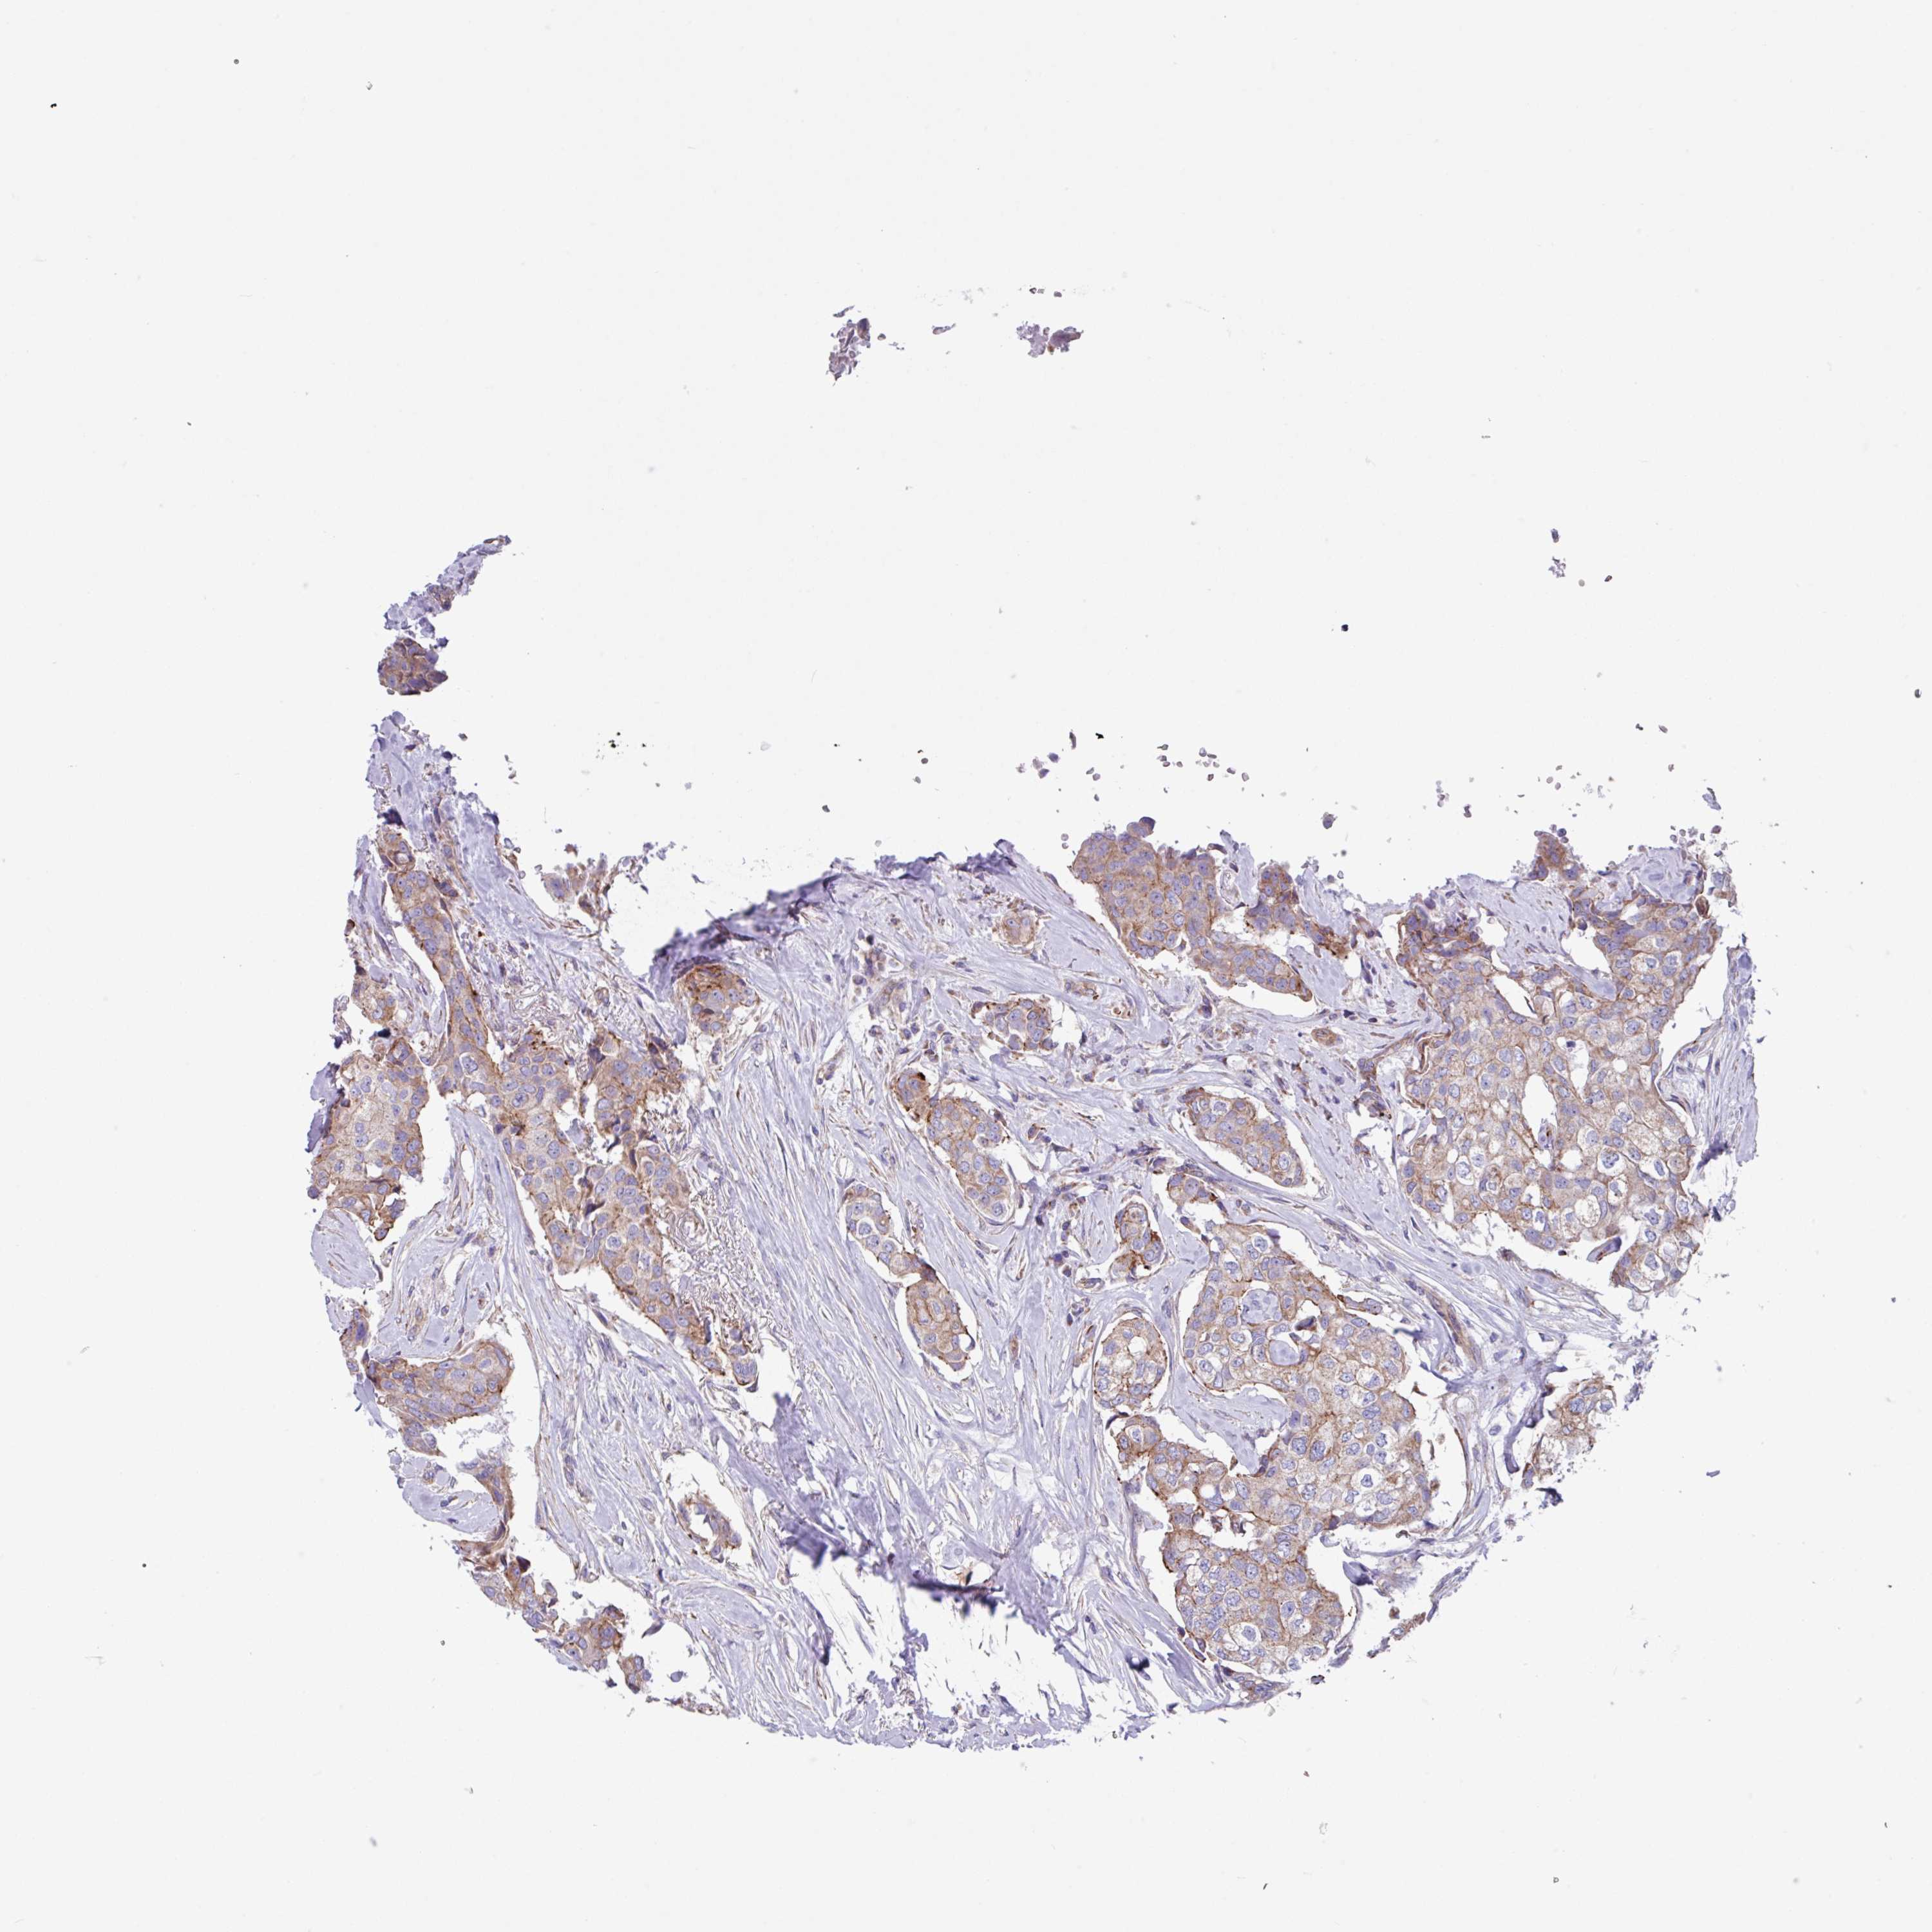

CANCER BREAST CANCER Show tissue menu

BRCA TCGA BRCA VALIDATION PROTEIN EXPRESSION

Breast cancer

Human cancer